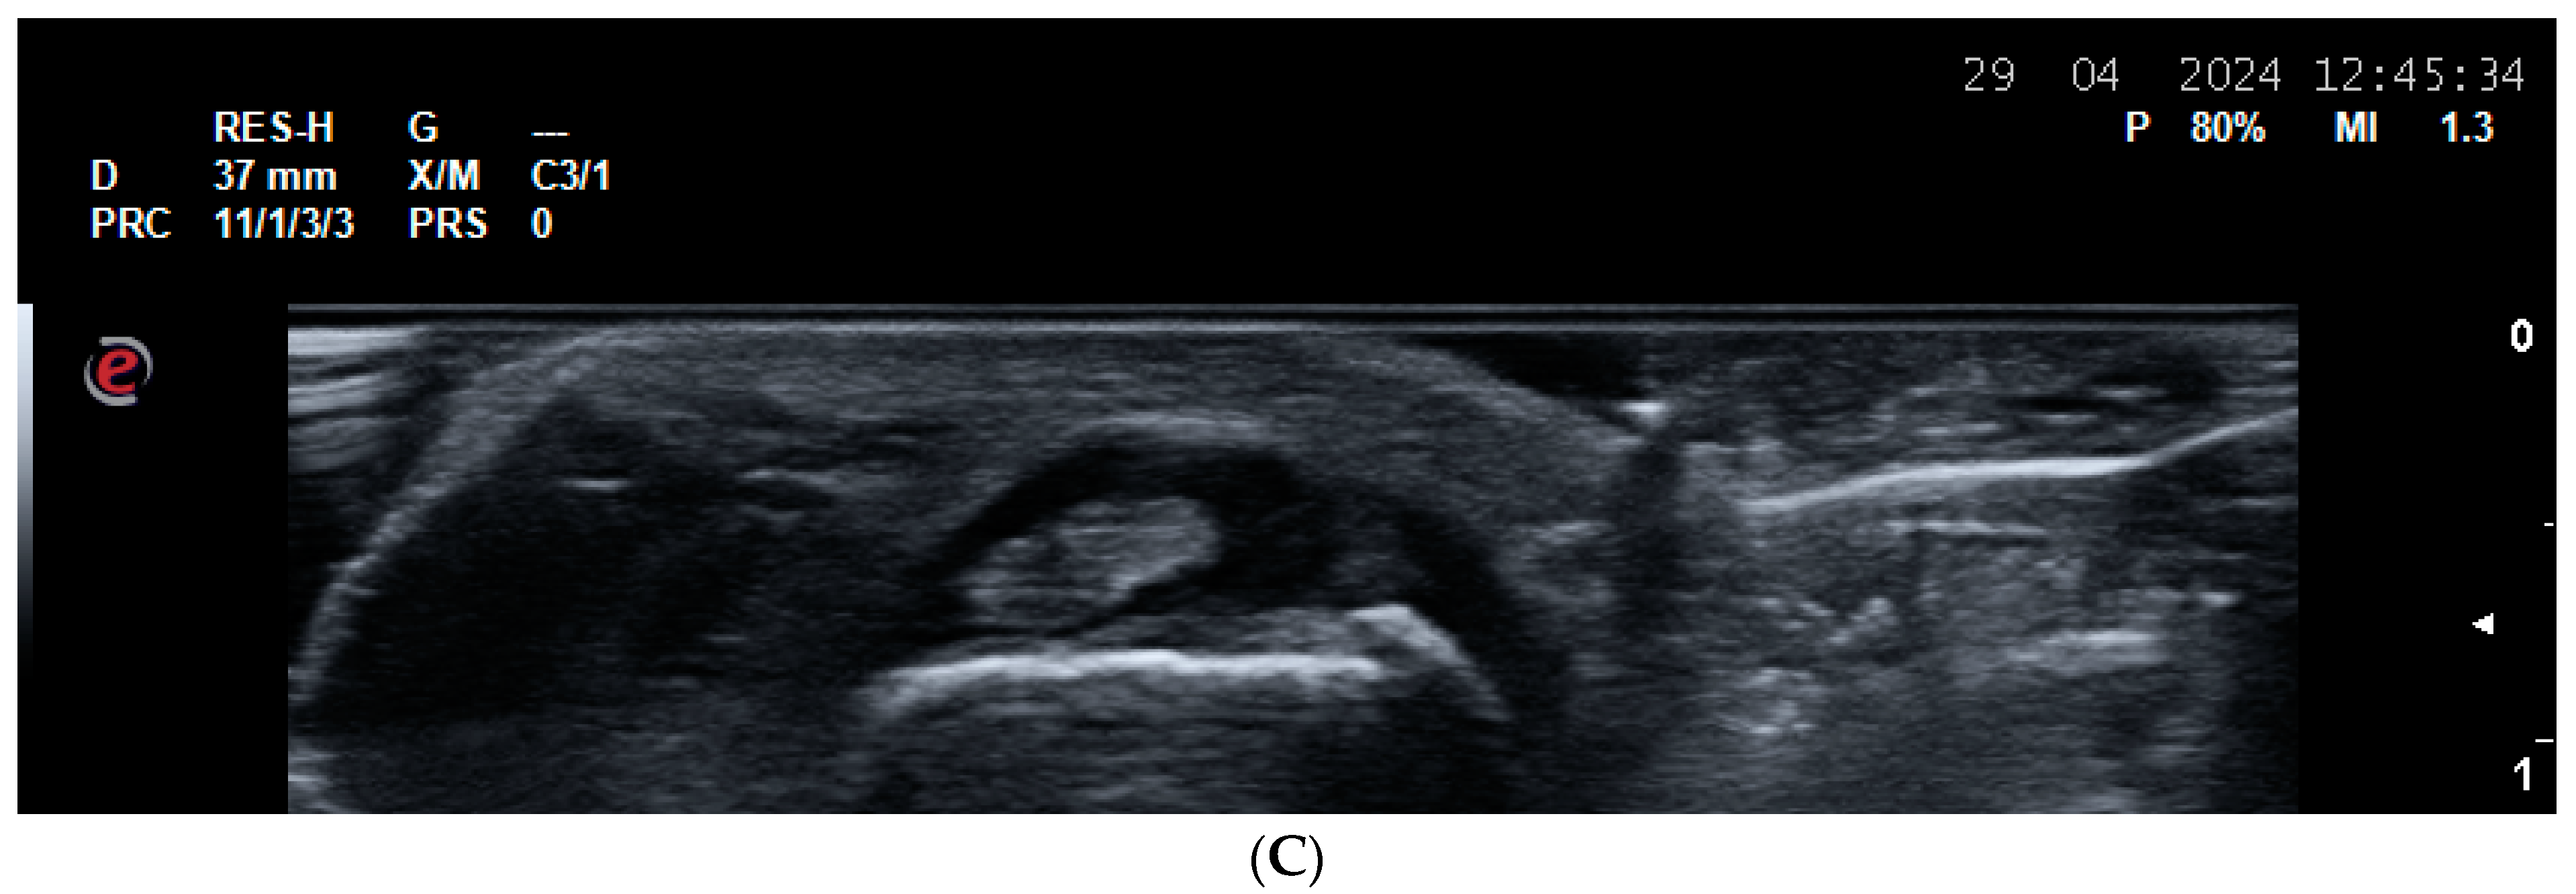

2.2. US for Assessment of Disease Activity and Monitoring Response to Therapy

- Agache, M.; Popescu, C.C.; Enache, L.; Mogoșan, C.; Filippucci, E.; Codreanu, C. Additional Value of Ultrasound in Patients with Psoriatic Arthritis within Treatment Target. J. Clin. Med. 2024, 13, 4567. [Google Scholar] [CrossRef] [PubMed] [PubMed Central]